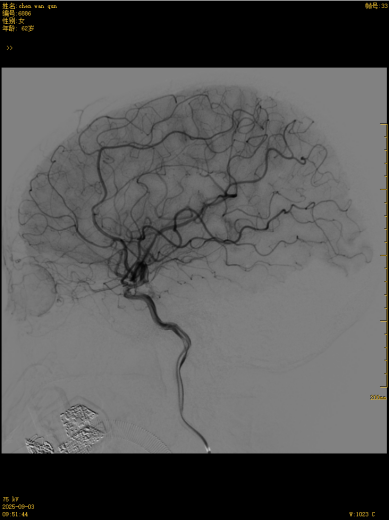

这款国产创新技术的优势不止于疗效:通体显影设计让支架定位精准到毫米级;超弹性材质与优化编织工艺实现极致贴壁,兼顾支撑力与柔顺性,适配复杂迂曲脑血管;操作更轻巧、创伤更小,仅需大腿根部米粒大小切口即可完成手术,可实现患者术后可快速康复。本次手术中,团队在DSA引导下精准释放支架,全程耗时短、出血少,术后造影显示,动脉瘤内血流即刻变得迟缓,载瘤动脉通畅,重要分支血管保护完好。患者术后恢复良好,未出现任何神经功能障碍,术后不久即快速康复出院,重获健康,恢复正常生活工作。